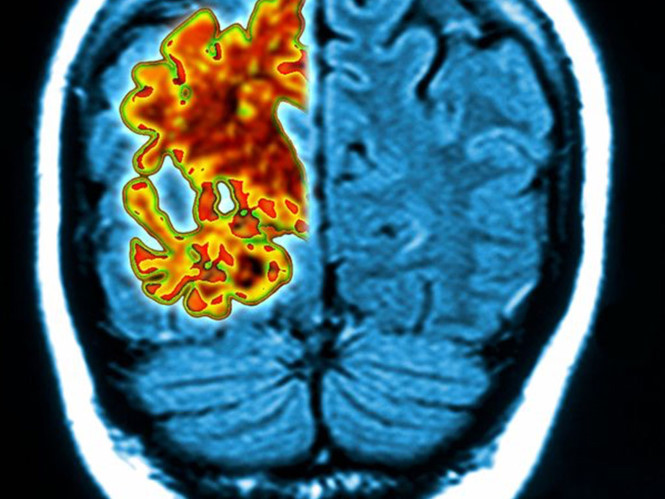

Bệnh mất trí nhớ không chỉ làm khổ người bệnh mà những người thân của họ hụt hẫng và khổ sở khi một ngày biết rằng họ bị mất trí nhớ. Thế nhưng nếu biết sớm thì vấn đề giải quyết sẽ không còn là quá khó. Một bài kiểm tra ngửi mùi đơn giản có thể giúp dự đoán chính xác bệnh mất trí nhớ trong 5 năm sau.

Một bài kiểm tra Ngửi mùi đơn giản có thể giúp dự đoán chính xác bệnh mất trí nhớ trong 5 năm sau. Bài kiểm tra này đã được các nhà nghiên cứu ở Mỹ thử nghiệm trên 3.000 người ở độ tuổi 57 đến 85.